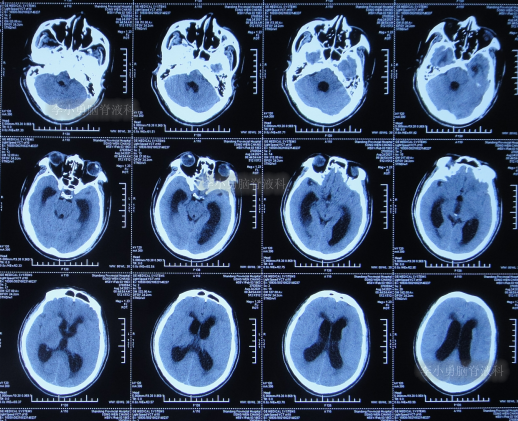

2021年8月28日(颈椎病术后3个月零21天并发颅内感染、脑积水),入院时:体温高,意识模糊,精神差,小便失禁,不能遵命活动,颈后有手术疤痕(图-3);入院时头颅CT示脑积水(图-4)。

图-4:入院时头颅CT

2021年8月30日(入院第2天),术前查颈椎影像示未见明显异常(图-5);进行了脑室外引流术(图-6)。

图-6:2021年8月30日术后头颅CT